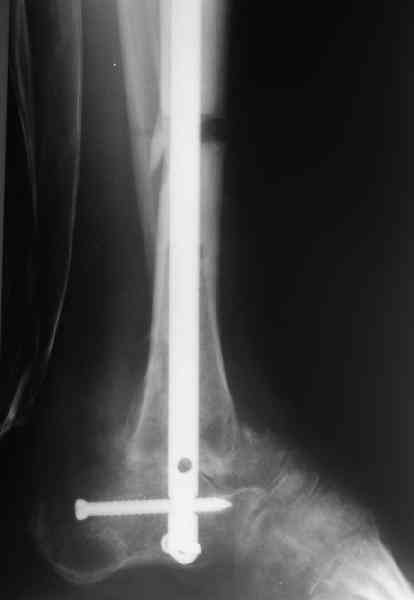

Аппарат был снят окончательно только после введения стержня, то есть оставалось по одной спице в проксимальном и дистальном метафизах большеберцовой кости, спицы в пятке. Фото во время рассверливания в приложении.

ВМ> 2. достаточно-ли одного проксимального статического винта,нет ли

ВМ> опасения проседания регенераратов и разрушения винта

Стержень 12 мм, винт диаметром 6 мм, костная трубка вокруг хорошая. Перелом такого винта пока не наблюдали ни разу на нескольких сотнях

пациентов.